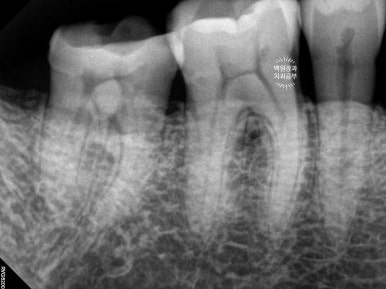

아래 어금니들은 위 어금니가 없는 사이에 너무 많이 정출되어 있었어요.

치아가 교합평면 (occlusal plain)을 기준으로 보았을 때 너무 튀어나왔기 때문에 깎아 내릴 필요가 있었어요.

(녹색 화살표로 표시해 둔 치아들은 3-4mm 이상 정출되어 있었어요. 대합치가 없기 때문이죠.)

다른 치과에서는 아래 어금니도 다 뽑고 임플란트를 하자고 하셨었는데, 치아들의 흔들거림이 없었기에 신경치료와 크라운치료로 아래 어금니들을 최대한 활용해보기로 계획했습니다.

왼쪽 아래 어금니들의 신경치료가 훌륭하게 성공적으로 진행되었습니다.

의도적 근관치료 (intentional root canal treatment)라고도 합니다.

오른쪽 아래 어금니들도 성공적으로 근관치료를 마쳤습니다.

신경치료를 마친 치아들은 통증을 느끼지 않는 상태가 되므로, 정출된 양을 모두 삭제하여 씌워도 아프지 않게 됩니다. 저희 환자분 같은 경우 치아 주변 치조골의 상태는 매우 양호하였으므로 의도적 근관치료를 동반한 보철치료를 선택한 것이 아주 적절하다고 볼 수 있지요.